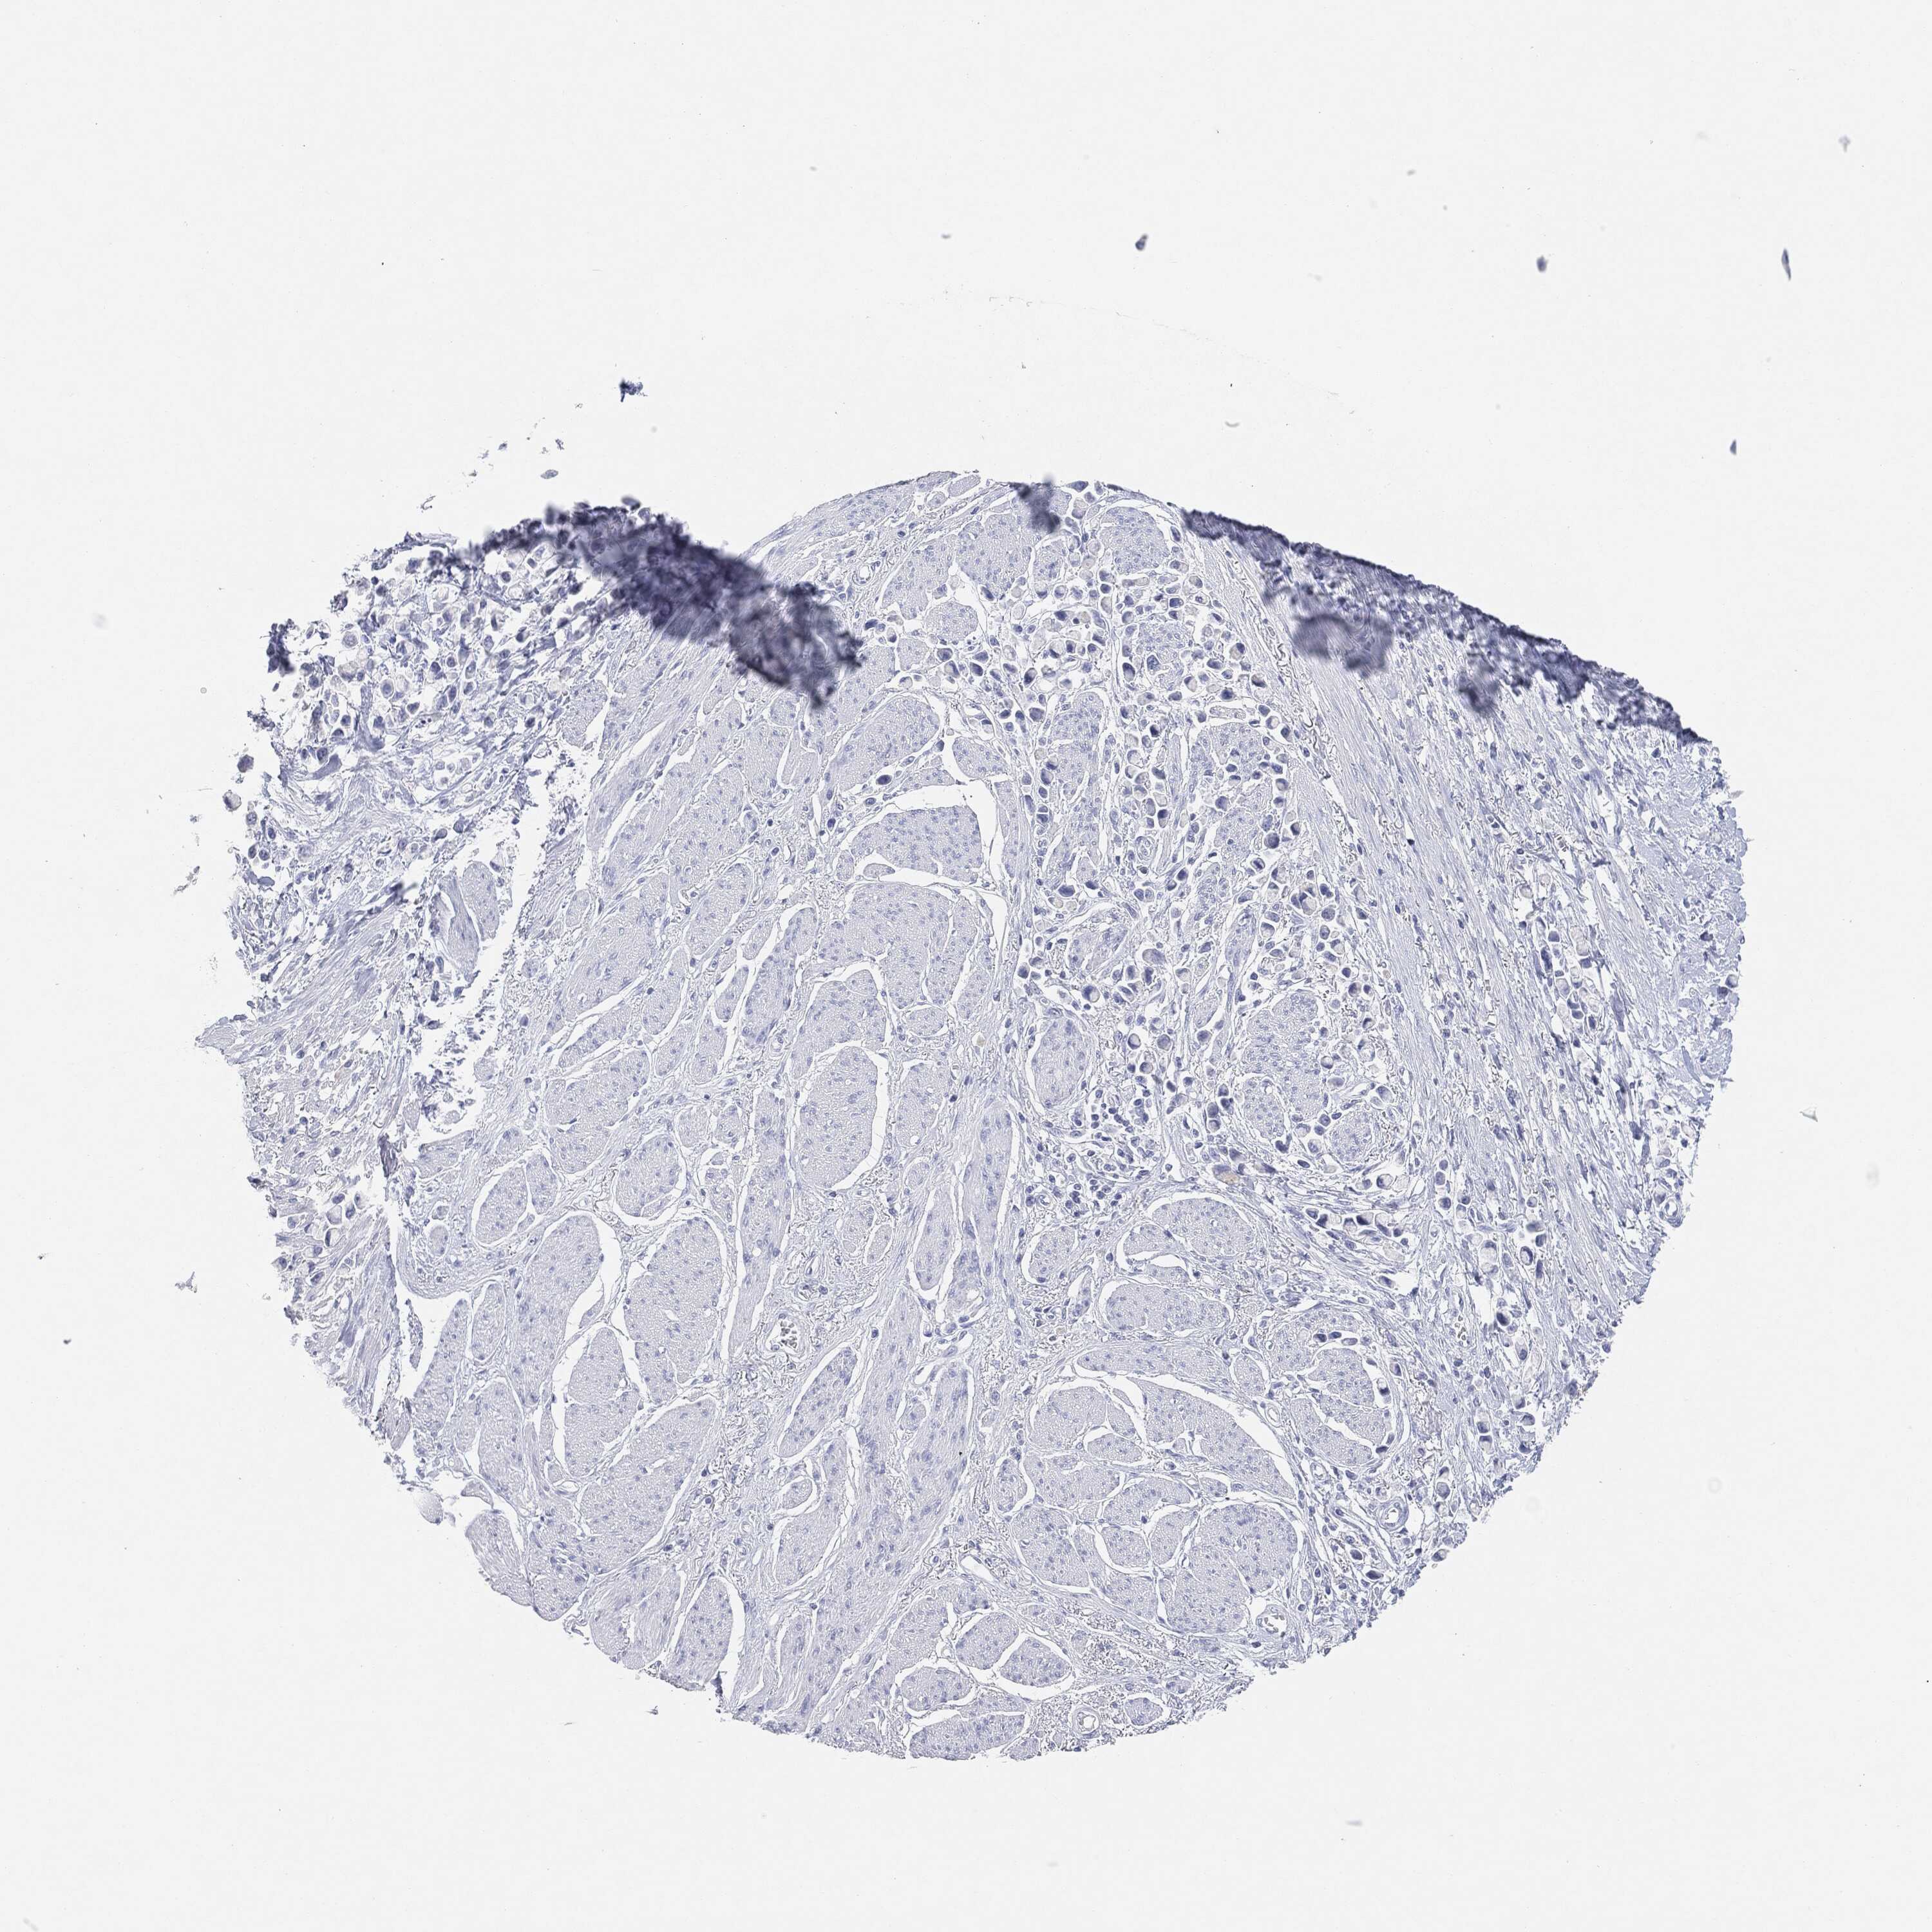

STOMACH CANCER - Protein expressioni

A mouse-over function shows sample information and annotation data. Click on an image to view it in a full screen mode. Samples can be filtered based on level of antibody staining by selecting one or several of the following categories: high, medium, low and not detected. The assay and annotation is described here.

Note that samples used for immunohistochemistry by the Human Protein Atlas do not correspond to samples in the TCGA dataset.

Antibody stainingi

Antibody staining in the annotated cell types in the current human tissue is reported as not detected, low, medium, or high, based on conventional immunohistochemistry profiling in selected tissues. This score is based on the combination of the staining intensity and fraction of stained cells.

Each image is clickable and will lead to virtual microscopy that enables deeper exploration of all samples and also displays staining intensity scores, fraction scores and subcellular localization as well as patient and tissue information for each sample.

Antibody HPA031634

Antibody CAB080501

Antibody CAB080502

Antibody CAB080503

Staining

High

Medium

Low

Not detected

Intensity

Strong

Moderate

Weak

Negative

Quantity

>75%

75%-25%

<25%

None

Location

Nuclear

Cytoplasmic/membranous

Cytoplasmic/membranous,nuclear

Adenocarcinoma, NOS

Adenocarcinoma, High grade